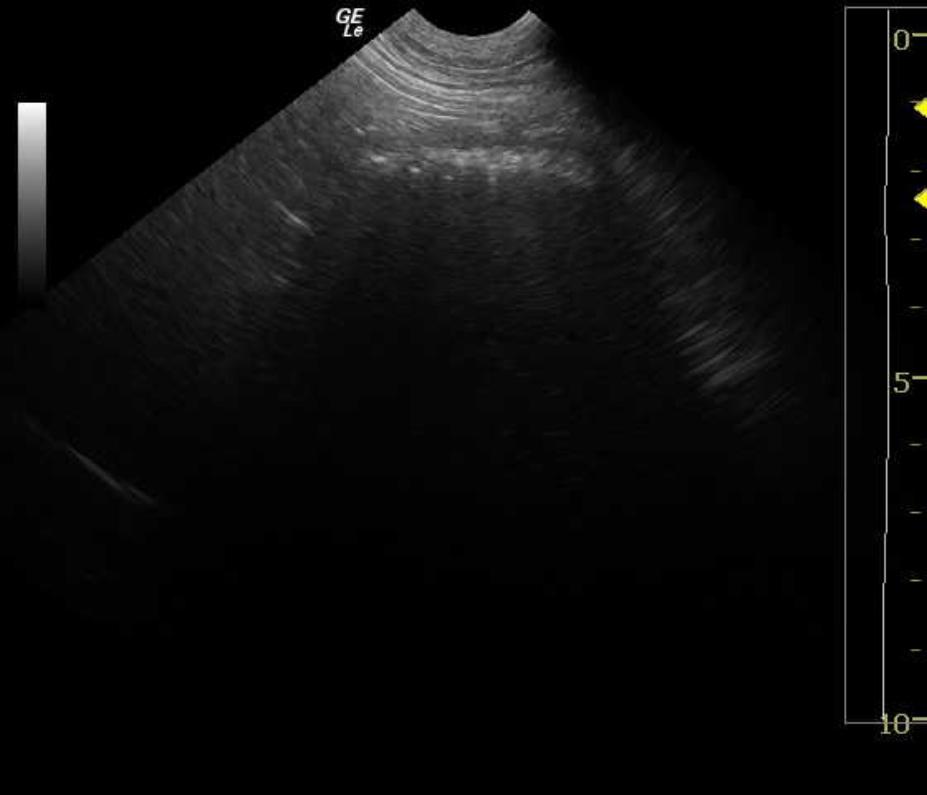

5 year old FS Labrador retriever was presented for repetitive vomiting, hematemesis, severe halitosis, lethargy and depression. Lateral and ventral/dorsal radiographs revealed a dilated stomach to four times its normal size, as well as dilated loops of bowel dorsal to the stomach. Hypokalemia and hypochloremia were present on the serum biochemical profile. Leukocytosis was present on the CBC and the SNAP 4DX® test was negative.